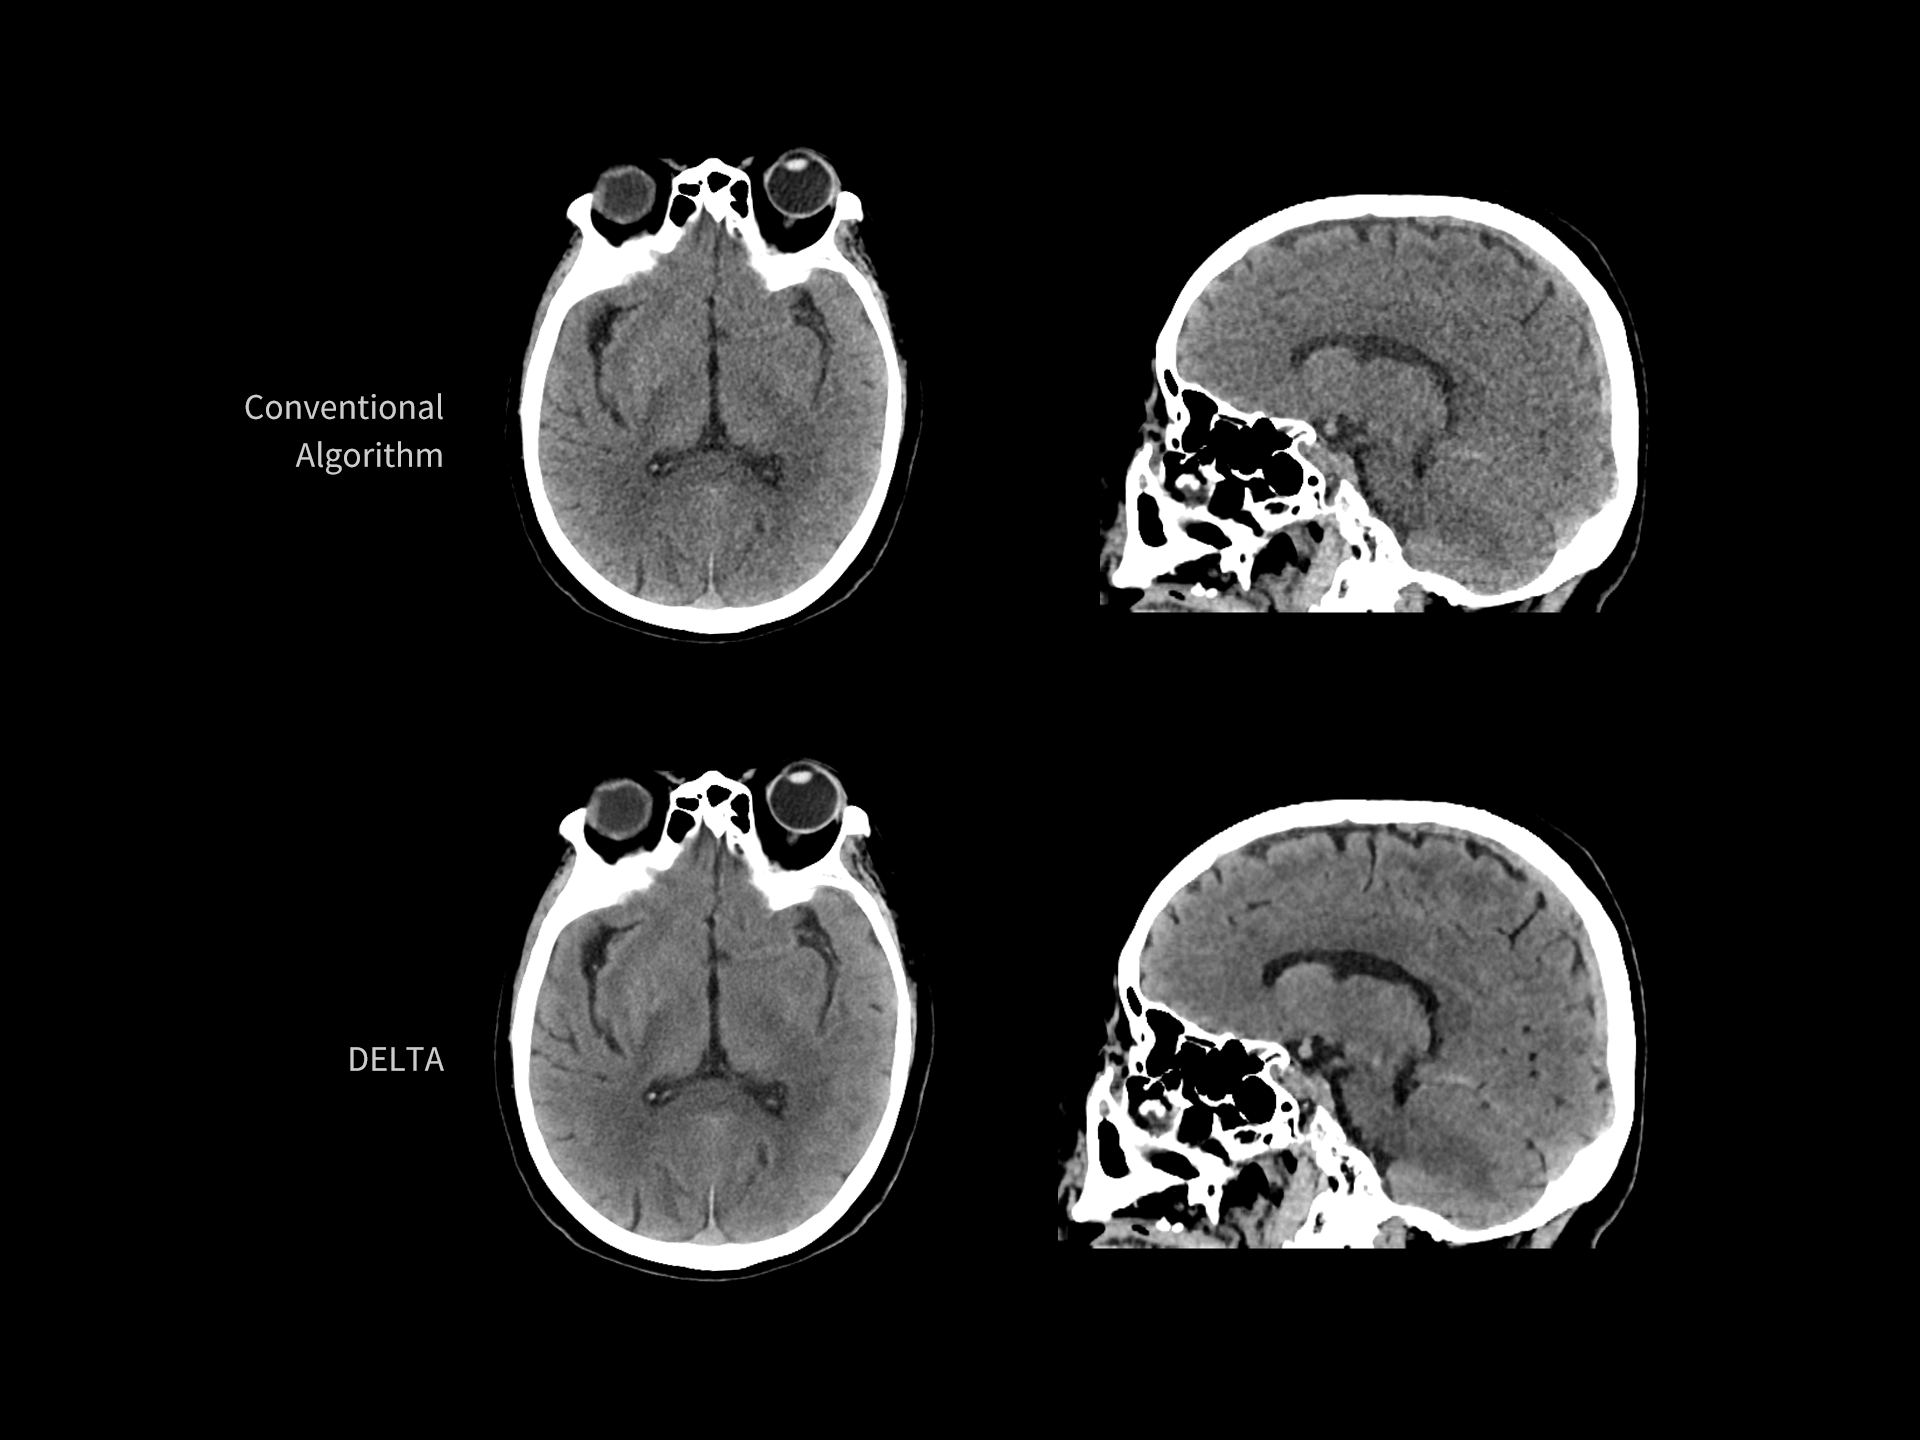

DELTA reduce zgomotul de imagine și îmbunătățește detectabilitatea contrastului redus

| Parametri scanare |

kV: 120 mAs: 101 CTDIvol: 8.8 mGy Doză efectivă: 6.3 mSv |

| Parametri reconstrucție |

Matrice: 512 × 512 Grosime secțiune: 1.0 × 0.8 mm HIR: B_VSOFT_B Nivel DL-Denoise: 3 WW/WL: 300/400 |

| Contrast | — |